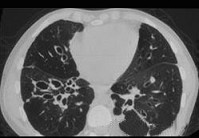

- 单项选择题男,18岁, 咳嗽,咳痰, 咯血半月余,CT如图.选出最可能的诊断 ( )

A、过敏性肺炎

B、支气管扩张

C、原发性肺结核

D、大叶性肺炎

E、肺癌